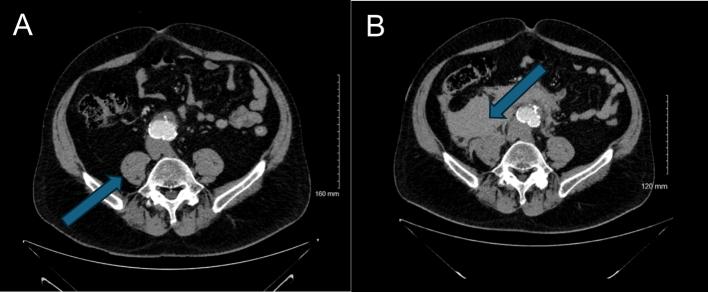

图 2 A 和 B:对比增强轴向计算机断层扫描的更远端视图

A 图为破裂前初始 CT 扫描:显示大型肾下型动脉瘤,瘤壁完整;B 图为患者动脉瘤破裂后病情恶化的后续扫描:显示右侧新发腹膜后血肿,对右侧腰大肌产生占位效应,符合破裂表现。A 图中箭头指向右侧腰大肌,B 图中箭头指向破裂性腹主动脉瘤所致血肿。

患者从CT室返回急诊科后,主诉睾丸疼痛急性加重,血流动力学不稳定,血压降至 60/30mmHg,但双侧股动脉搏动仍可触及。其他生命体征为:心率55次/分钟,室内空气下血氧饱和度95%。患者出现嗜睡、意识模糊,情况危急。医院立即启动复苏措施,并将患者送回CT室紧急复查。复查影像显示动脉瘤囊右侧出现新发腹膜后出血(分别见图1A与图1B、图2A与图2B对比)。患者被直接转运至急诊手术室,启动大量输血方案,并通知手术室工作人员、麻醉团队及高级外科医师。本次诊断的主要挑战是从孤立性睾丸疼痛中识别出症状性腹主动脉瘤。

睾丸疼痛是急诊科常见的泌尿系统疾病特征性症状,如睾丸扭转、附睾炎、鞘膜积液或尿路结石等。关于症状性腹主动脉瘤患者出现孤立性睾丸疼痛的病因,一种假说认为是动脉瘤囊刺激生殖股神经所致,血肿或局部出血可能进一步压迫神经。生殖股神经起源于腰丛 L1/L2 节段,沿腹后壁下行,经腰大肌前表面,随后分为生殖支和股支。生殖支负责阴囊的感觉传导,并支配提睾肌。本例患者的横断面CT影像显示,右侧腰大肌被血肿浸润(图 1B、图 2B)。故推测动脉瘤囊或血肿的局部刺激可能引发睾丸牵涉痛。主动脉通常位于腹部中线左侧,因此症状性腹主动脉瘤患者的睾丸疼痛非典型表现更常见于左侧,这也使得本病例的非典型性更为显著。尽管该假说仍为推测,但影像中腰大肌区域受累及其与生殖股神经的邻近关系支持这一解释。生殖股神经痛相关研究也为该疼痛的解剖学基础提供了佐证——生殖股神经痛是指因生殖股神经受压或损伤引发的神经病理性疼痛,症状包括阴囊疼痛。然而,大多数关于生殖股神经痛的文献聚焦于医源性损伤,而非血管压迫。